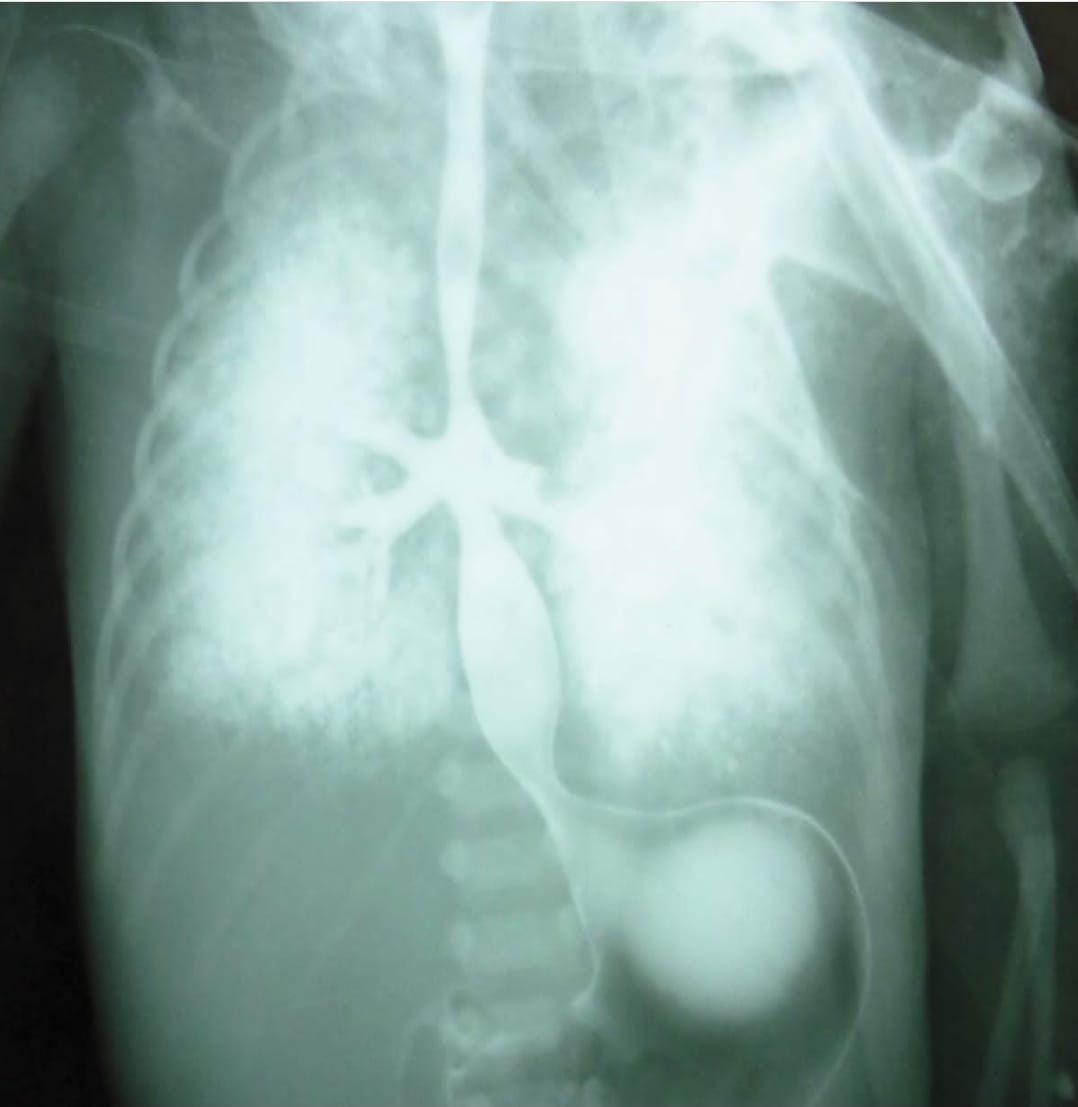

Radiografia con mezzo di contrasto di neonato prematuro (32 settimane). Il neonato presentava una malformazione congenita (il che significa che era già presente alla nascita) chiamata agenesia tracheale, cioè mancanza della trachea, con fusione tra i due bronchi destro e sinistro e fistola bronco-esofagea (comunicazione anomala tra bronchi ed esofago). La madre del neonato aveva il diabete e non erano presenti altri casi di agenesia tracheale in famiglia. La prevalenza alla nascita dell’agenesia tracheale è di circa 1 su 50.000. Nel 90% dei casi sono presenti più malformazioni congenite associate, che vanno a determinare la sindrome di VATER.

Purtroppo non esiste una soluzione chirurgica a lungo termine all’agenesia della trachea, in quanto ad oggi non è disponibile un materiale adatto per una protesi della trachea. Questa malformazione è di solito fatale nei neonati, salvo rarissimi casi, tanto che la diagnosi è – nella maggioranza dei casi – effettuata post mortem. Il piccolo a cui appartiene questa radiografia, è purtroppo morto soffocato.

Il cariotipo del neonato ha evidenziato una malattia genetica nota come sindrome di Edwards o “trisomia 18“, caratterizzata dalla presenza di tre cromosomi 18 anziché due.